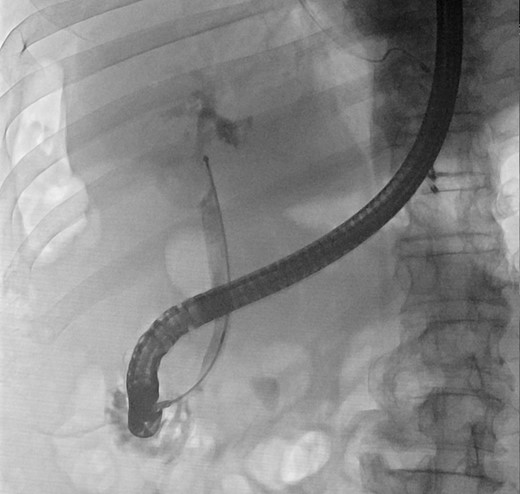

We report a case of a 67-year-old man, who presented with fever, chills and jaundice to a local district hospital. He had a temperature of 39°C and new-onset atrial fibrillation. Examination of the abdomen showed no peritoneal signs. Blood biochemistry demonstrated leukocytosis and abnormal liver function tests: bilirubin 75 μmol/L, alkaline phosphatase 1018 unit/L, alanine transaminase 177 unit/L. Ultrasound scan showed a 3 cm gallstone without common bile duct dilatation. However, computed tomography of abdomen revealed a gallstone eroding into the CHD, causing intrahepatic ductal dilatation (Fig. 1). The diagnosis of type II Mirizzi syndrome was confirmed by endoscopic retrograde cholangiopancreatography (ERCP), where cholangiogram demonstrated a gallstone fistulating into the CHD (Fig. 2). Biliary stent was inserted and intravenous antibiotics were given to tie over this acute episode of cholangitis.

Computed tomography of the abdomen showing a gallstone compressing onto the common hepatic duct.